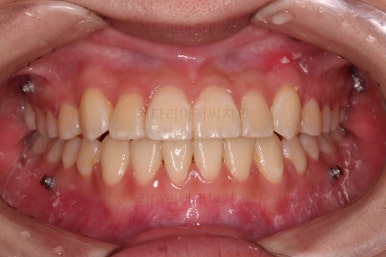

덧니가 완전히 개선디ㅗ었고 필요한 충치치료도 부분적으로 진행했고요.

중앙선이나 교합도 양호하게 마무리 했습니다.

환자분이 원하는 포인트들이 다 개선되었고요.

웃을 때 보이는 느낌도 많이 좋아졌네요.

옆라인도 입이 안나오게 비발치 교정 마무리 잘 되었고요.